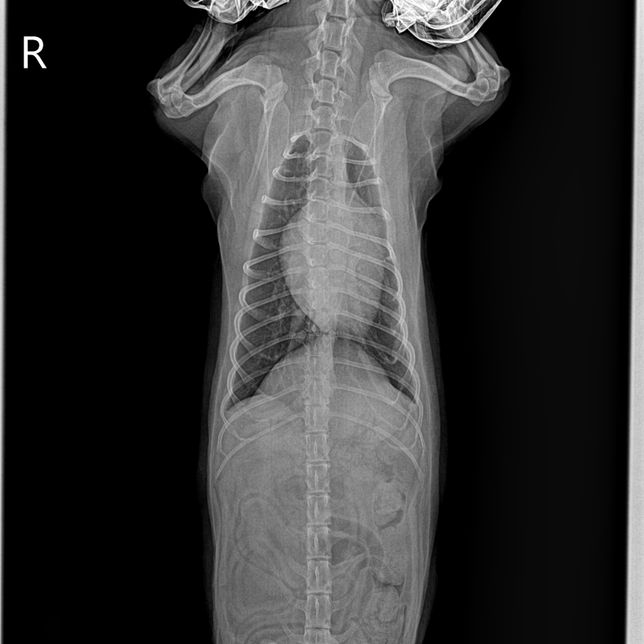

- 반려동물 건강반려동물Q. (이은수 수의사님) 하나만 더 여쭤보고싶습니다ㅠ 강아지 엑스레이 관련안녕하세요 강아지 건강검진 받고 엑스레이상 흉골이 휘었다고 했었는데요, 외부충격은 없고, 1년 전 다른 병원에서 찍은 엑스레이는 흉골 휘지 않았습니다. 사진상으로 휘어보이는거라고 하셨는데 잘못찍혔다는 말씀이실까요? 건강검진 병원에서는 1년전 다른 병원에서 찍은 엑스레이는 흉골이 휘지 않아서 폐쪽 문제일수도 있으니 ct가능한 병원가서 정확하게 보는게 좋을거같다는데, 폐에 문제가 생기면 심장이 쏠리면서 흉골이 휠수도있나요..? 엑스레이는 흉골이 휜거같아 이상해서 세번정도 찍었다고 하네요. 사진 보면 노란색 표시 흉골이 휘어있고 심장도 쏠려있습니다…잘못찍었다고 흉골이 휘고 심장도 쏠릴 수 있나요?!?첫번째 사진이 1년전 다른병원에서 찍은 엑스레이고 2,3번째가 이번에 찍은 흉골 휜 엑스레이입니다.. 3,4번째 흉골 휜 엑스레이 같은 사진인데 휜 흉골부분 노란색으로 표시해뒀습니다. R, L사진 둘 다 다른방향에서 찍은거같은데, 둘 다 휘어있습니다. 폐쪽의 문제일수도 있을까요? 기침이나 식욕감퇴 등의 다른 증상은 없고 변 상태도 좋습니다.

- 반려동물 건강반려동물Q. 강아지 엑스레이 잘못찍으면 흉골 휘어보이게 나오는건가요안녕하세요 강아지 건강검진 받고 엑스레이상 흉골이 휘었다고 했었는데요, 외부충격은 없고, 1년 전 다른 병원에서 찍은 엑스레이는 흉골 휘지 않았습니다. 사진상으로 휘어보이는거라고 하셨는데 잘못찍혔다는 말씀이실까요? 건강검진 병원에서는 1년전 다른 병원에서 찍은 엑스레이는 흉골이 휘지 않아서 폐쪽 문제일수도 있으니 ct가능한 병원가서 정확하게 보는게 좋을거같다는데, 폐에 문제가 생기면 심장이 쏠리면서 흉골이 휠수도있나요..? 엑스레이는 흉골이 휜거같아 이상해서 세번정도 찍었다고 하네요. 사진 보면 노란색 표시 흉골이 휘어있고 심장도 쏠려있습니다…잘못찍었다고 흉골이 휘고 심장도 쏠릴 수 있나요?!?첫번째 사진이 1년전 다른병원에서 찍은 엑스레이고 2,3번째가 이번에 찍은 흉골 휜 엑스레이입니다.. 3,4번째 흉골 휜 엑스레이 같은 사진인데 휜 흉골부분 노란색으로 표시해뒀습니다. R, L사진 둘 다 다른방향에서 찍은거같은데, 둘 다 휘어있습니다. 폐쪽의 문제일수도 있을까요? 기침이나 식욕감퇴 등의 다른 증상은 없고 변 상태도 좋습니다.

- 반려동물 건강반려동물Q. 강아지 엑스레이 흉골이 휘었다는데오안녕하세요 강아지 건강검진 받고 엑스레이상 흉골이 휘었다고 했었는데요, 외부충격은 없고, 1년 전 다른 병원에서 찍은 엑스레이는 흉골 휘지 않았습니다. 사진상으로 휘어보이는거라고 하셨는데 잘못찍혔다는 말씀이실까요? 건강검진 병원에서는 1년전 다른 병원에서 찍은 엑스레이는 흉골이 휘지 않아서 폐쪽 문제일수도 있으니 ct가능한 병원가서 정확하게 보는게 좋을거같다는데, 폐에 문제가 생기면 심장이 쏠리면서 흉골이 휠수도있나요..? 엑스레이는 흉골이 휜거같아 이상해서 세번정도 찍었다고 하네요. 사진 보면 노란색 표시 흉골이 휘어있고 심장도 쏠려있습니다…잘못찍었다고 흉골이 휘고 심장도 쏠릴 수 있나요?!? 첫번째 사진이 1년전 다른병원에서 찍은 엑스레이고 2,3번째가 이번에 찍은 흉골 휜 엑스레이입니다.. 3,4번째 흉골 휜 엑스레이 같은 사진인데 휜 흉골부분 노란색으로 표시해뒀습니다. R, L사진 둘 다 다른방향에서 찍은거같은데, 둘 다 휘어있습니다. 폐쪽의 문제일수도 있을까요? 기침이나 식욕감퇴 등의 다른 증상은 없고 변 상태도 좋습니다.

- 반려동물 건강반려동물Q. 강아지 엑스레이 흉골 휘었다는데요 ..안녕하세요 강아지 건강검진을했는데 흉골이 휘었다고해서요. 첫번째사진은 1년전이고 2,3번째 사진은 이번년도 사진입니다. 혹시 이런경우 원인은 무엇인가요? 외부충격은 없었습니다..

- 반려동물 건강반려동물Q. 강아지 엑스레에 찍을 때 자세 이상하면 흉골이 휘어보이게 나올수도 있나요? 강아지 엑스레에 찍을 때 자세 이상하면 흉골이 휘어보이게 나올수도 있나요? 건강검진 했는데 흉골이 휘었대서요.. 작년 다른 병원에서 검진했을 때는 괜찮았는데 외부충격도 없었는데 1년만에 휘을수가있나요.?.. 외부 충격 아니면 폐쪽 문제일수도있다는데 외부충격은 없었고, 기침이나 다른 증상도 없어서요. 혹시 엑스레이 찍을 때 자세가 잘못되면 흉골이 휘게 나오기도 하나요